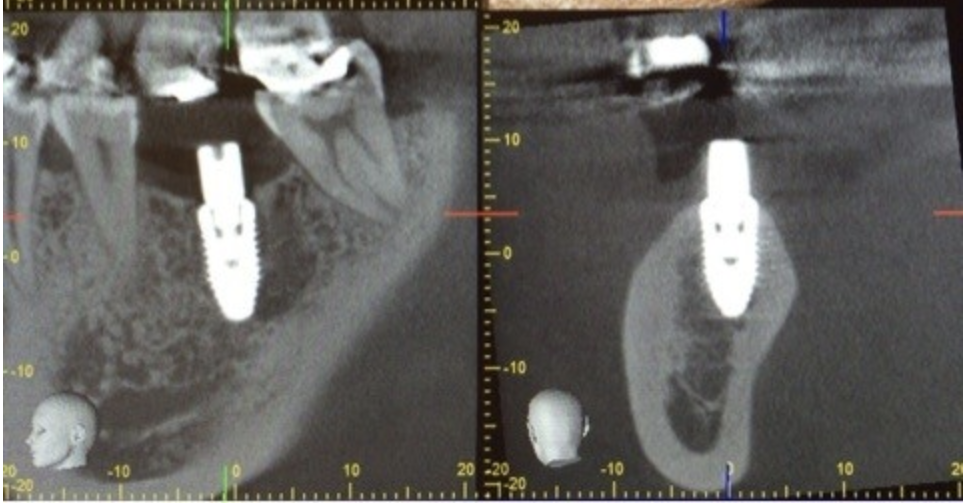

それでは当院でのインプラント手術の例です。

患者様は左下の奥歯が欠損してしまい、しっかり食事を摂りたいという希望で無痛治療でのインプラント手術を選択されました。

術前に綿密にシミュレーションを行っていたものとほぼ同じ位置に埋入されていることが確認できます。

今回は埋入手術の話ですが、当院では上記にお話ししたインプラントの成立要件を全て確認し、シミュレーションを行い手術を行っています。